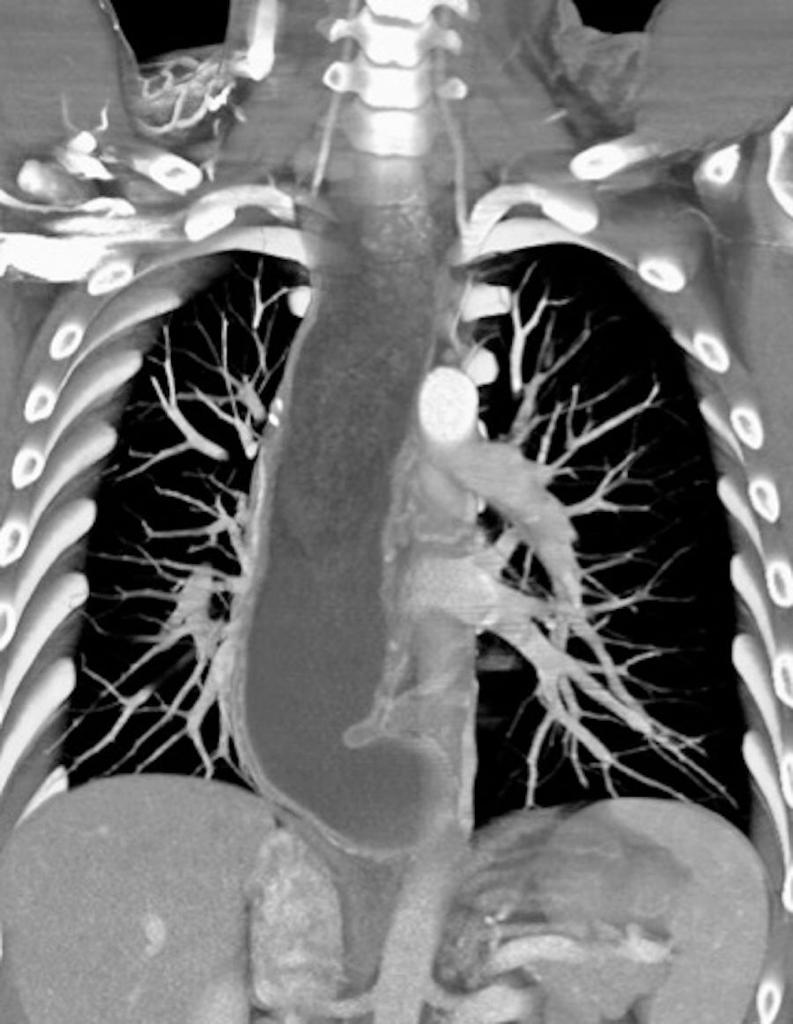

La Acalasia es un trastorno poco frecuente, que dificulta el paso de alimentos y líquidos hacia el estómago. La acalasia se presenta cuando se dañan los nervios del esófago. En consecuencia, el esófago pierde la capacidad de empujar el alimento hacia abajo, y la válvula muscular que se encuentra entre el esófago y el estómago( esfínter esofágico inferior) no se relaja por completo, lo que dificulta que el alimento llegue al estómago.